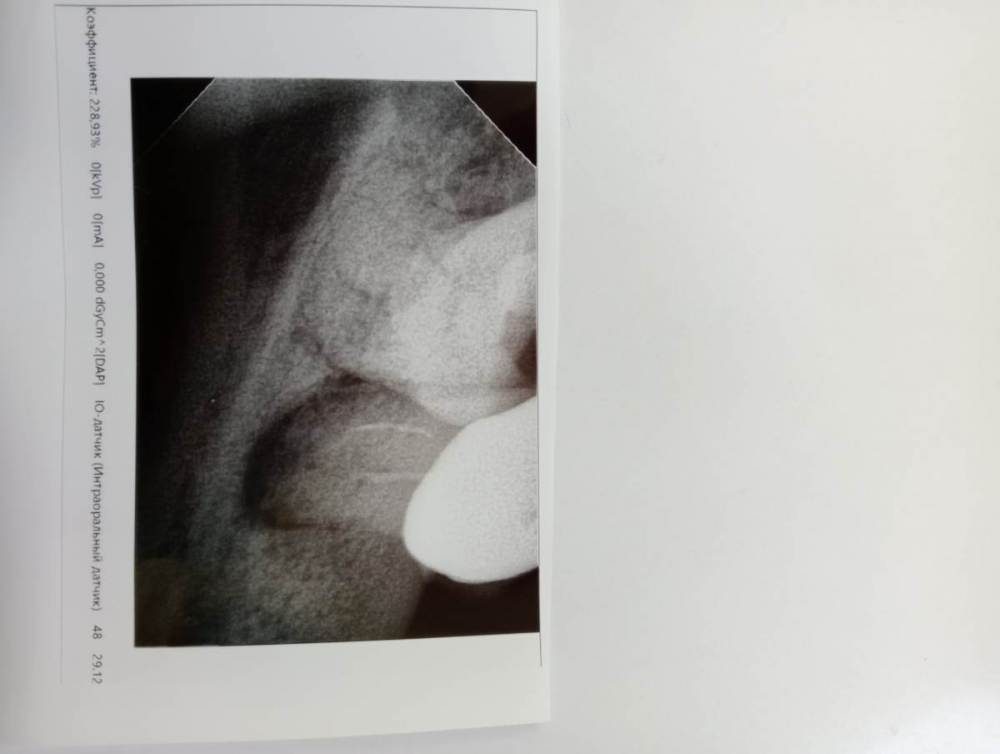

Маri 13 Опубликовано 23 января, 2023 Поделиться Опубликовано 23 января, 2023 Здравствуйте! Подскажите, удалять ли зуб ? Нижняя 7-ка под коронкой. Киста уже лет 7, не беспокоила и не росла. Два года назад перед установкой коронки перелечивали каналы, стала меньше, но до конца не прошла. Сейчас сказали, что воспаление ( это помимо кисты что-ли , или кисту и имели ввиду ? ) и надо удалять зуб. Зуб не болит, слегка пошатывается, но возможно из-за проблемных десен. Ссылка на комментарий

red_butler Опубликовано 24 января, 2023 Поделиться Опубликовано 24 января, 2023 26 минут назад, Маri 13 сказал: Так это все же киста на снимке или какое-то другое воспаление? это хронический апекальный периодонтит 27 минут назад, Маri 13 сказал: И можно ли убрать это воспаление хирургическим путем ( разрезав десну ) не снимая коронки и не перелечивая каналы? можно, но без перелечивания корневых каналов это малоэффективно Ссылка на комментарий